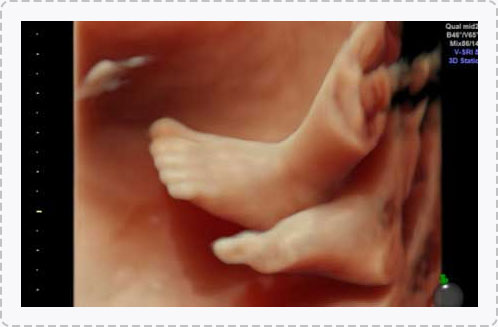

四维彩超能够直观、立体地显示人体器官的三维结构以及动态,实时地观察立体结构,被广泛用于检查胎儿发育状况,立体观察胎儿在子宫内发育情况的同时,还能够清晰显示胎儿在子宫内的动态,让准爸妈们一起观看宝宝在妈妈肚子里的动作、神态,还可将这个过程制作成光碟保存,让宝宝能够拥有完整的0岁相册,留下珍贵的纪念。

宝宝的0岁写真,是值得每个父母珍藏的。

一般情况下四维彩超的检查时间是孕22-28周,这段时间检查,胎儿大小适合,羊水适中,胎儿活动度大,体表也比较丰满,有利于胎儿四维超声成像和畸形筛查,是合适的检查时期。